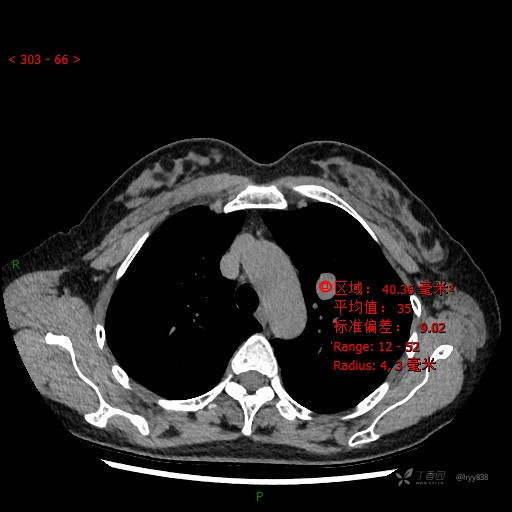

CT值